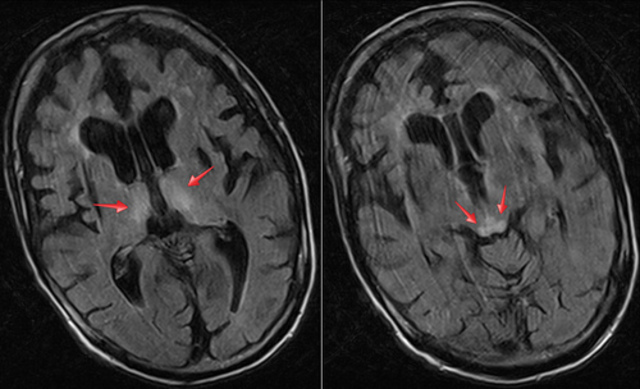

• Agentes infecciosos en el SN

Agentes infecciosos en el SN

Los agentes infecciosos responsable de las encefalopatias producen la enfermedad porque se replican en los tejidos del sistema nervioso